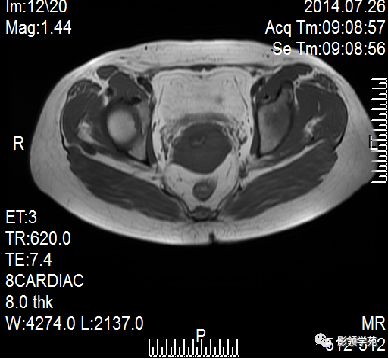

- 扫描序列:SAG T2WI,AXI T1WI+T2WI, COR T2WI 。其中SAG T2WI最重要

T1WI:呈均匀低信号,周围为高信号脂肪

卵巢:轴位和冠状面显示较佳,T1WI为中等或稍低信号,T2WI可因多个卵泡结构表现为高信号,但其间质部分仍呈稍低信号

宫颈癌可表现为类圆形或不规则形肿块,在T2WI上表现为均匀或欠均匀的高信号,与正常宫颈基质及宫旁脂肪形成良好的自然对比。